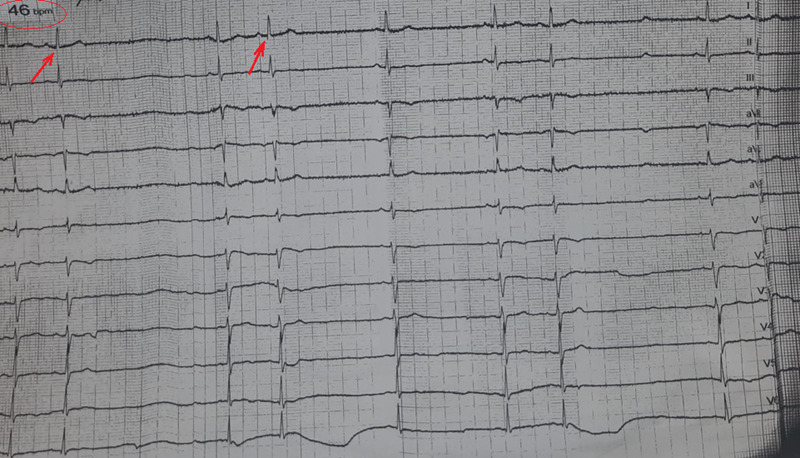

Glioblastoma represents the most common and aggressive primary malignant central nervous system tumor, often manifesting with unusual signs. This case report highlights a patient diagnosed with glioblastoma following an unusual cardiac presentation, with syncopes, sinus bradycardia, and atrial bigeminy. A 51-year-old female, brought to the emergency room after experiencing repeated syncope episodes, displayed neurological deficits upon examination. Noteworthy, she presented abnormal ECG showing sinus bradycardia and atrial bigeminy. Following the diagnostic procedure, a tumor was identified with indication to surgical removal. A subtotal tumor resection was obtained and the morphopathology examination led to a glioblastoma diagnosis. Interestingly, post-operatively, the ECG was completely normalized. However, the patient experienced complications, consisting of a massive thromboembolism. While sporadic cases describe unusual glioblastoma manifestations, this report is unique in showcasing atrial bigeminy, among other ECG manifestation. The remission of atrial bigeminy post-operatively suggests its association with the glioblastoma. Tumor localization in the basal ganglia is crucial in understanding such manifestations. Idiopathic cardiac manifestations should not be disregarded, holding potential relevance in central nervous system etiology considerations.